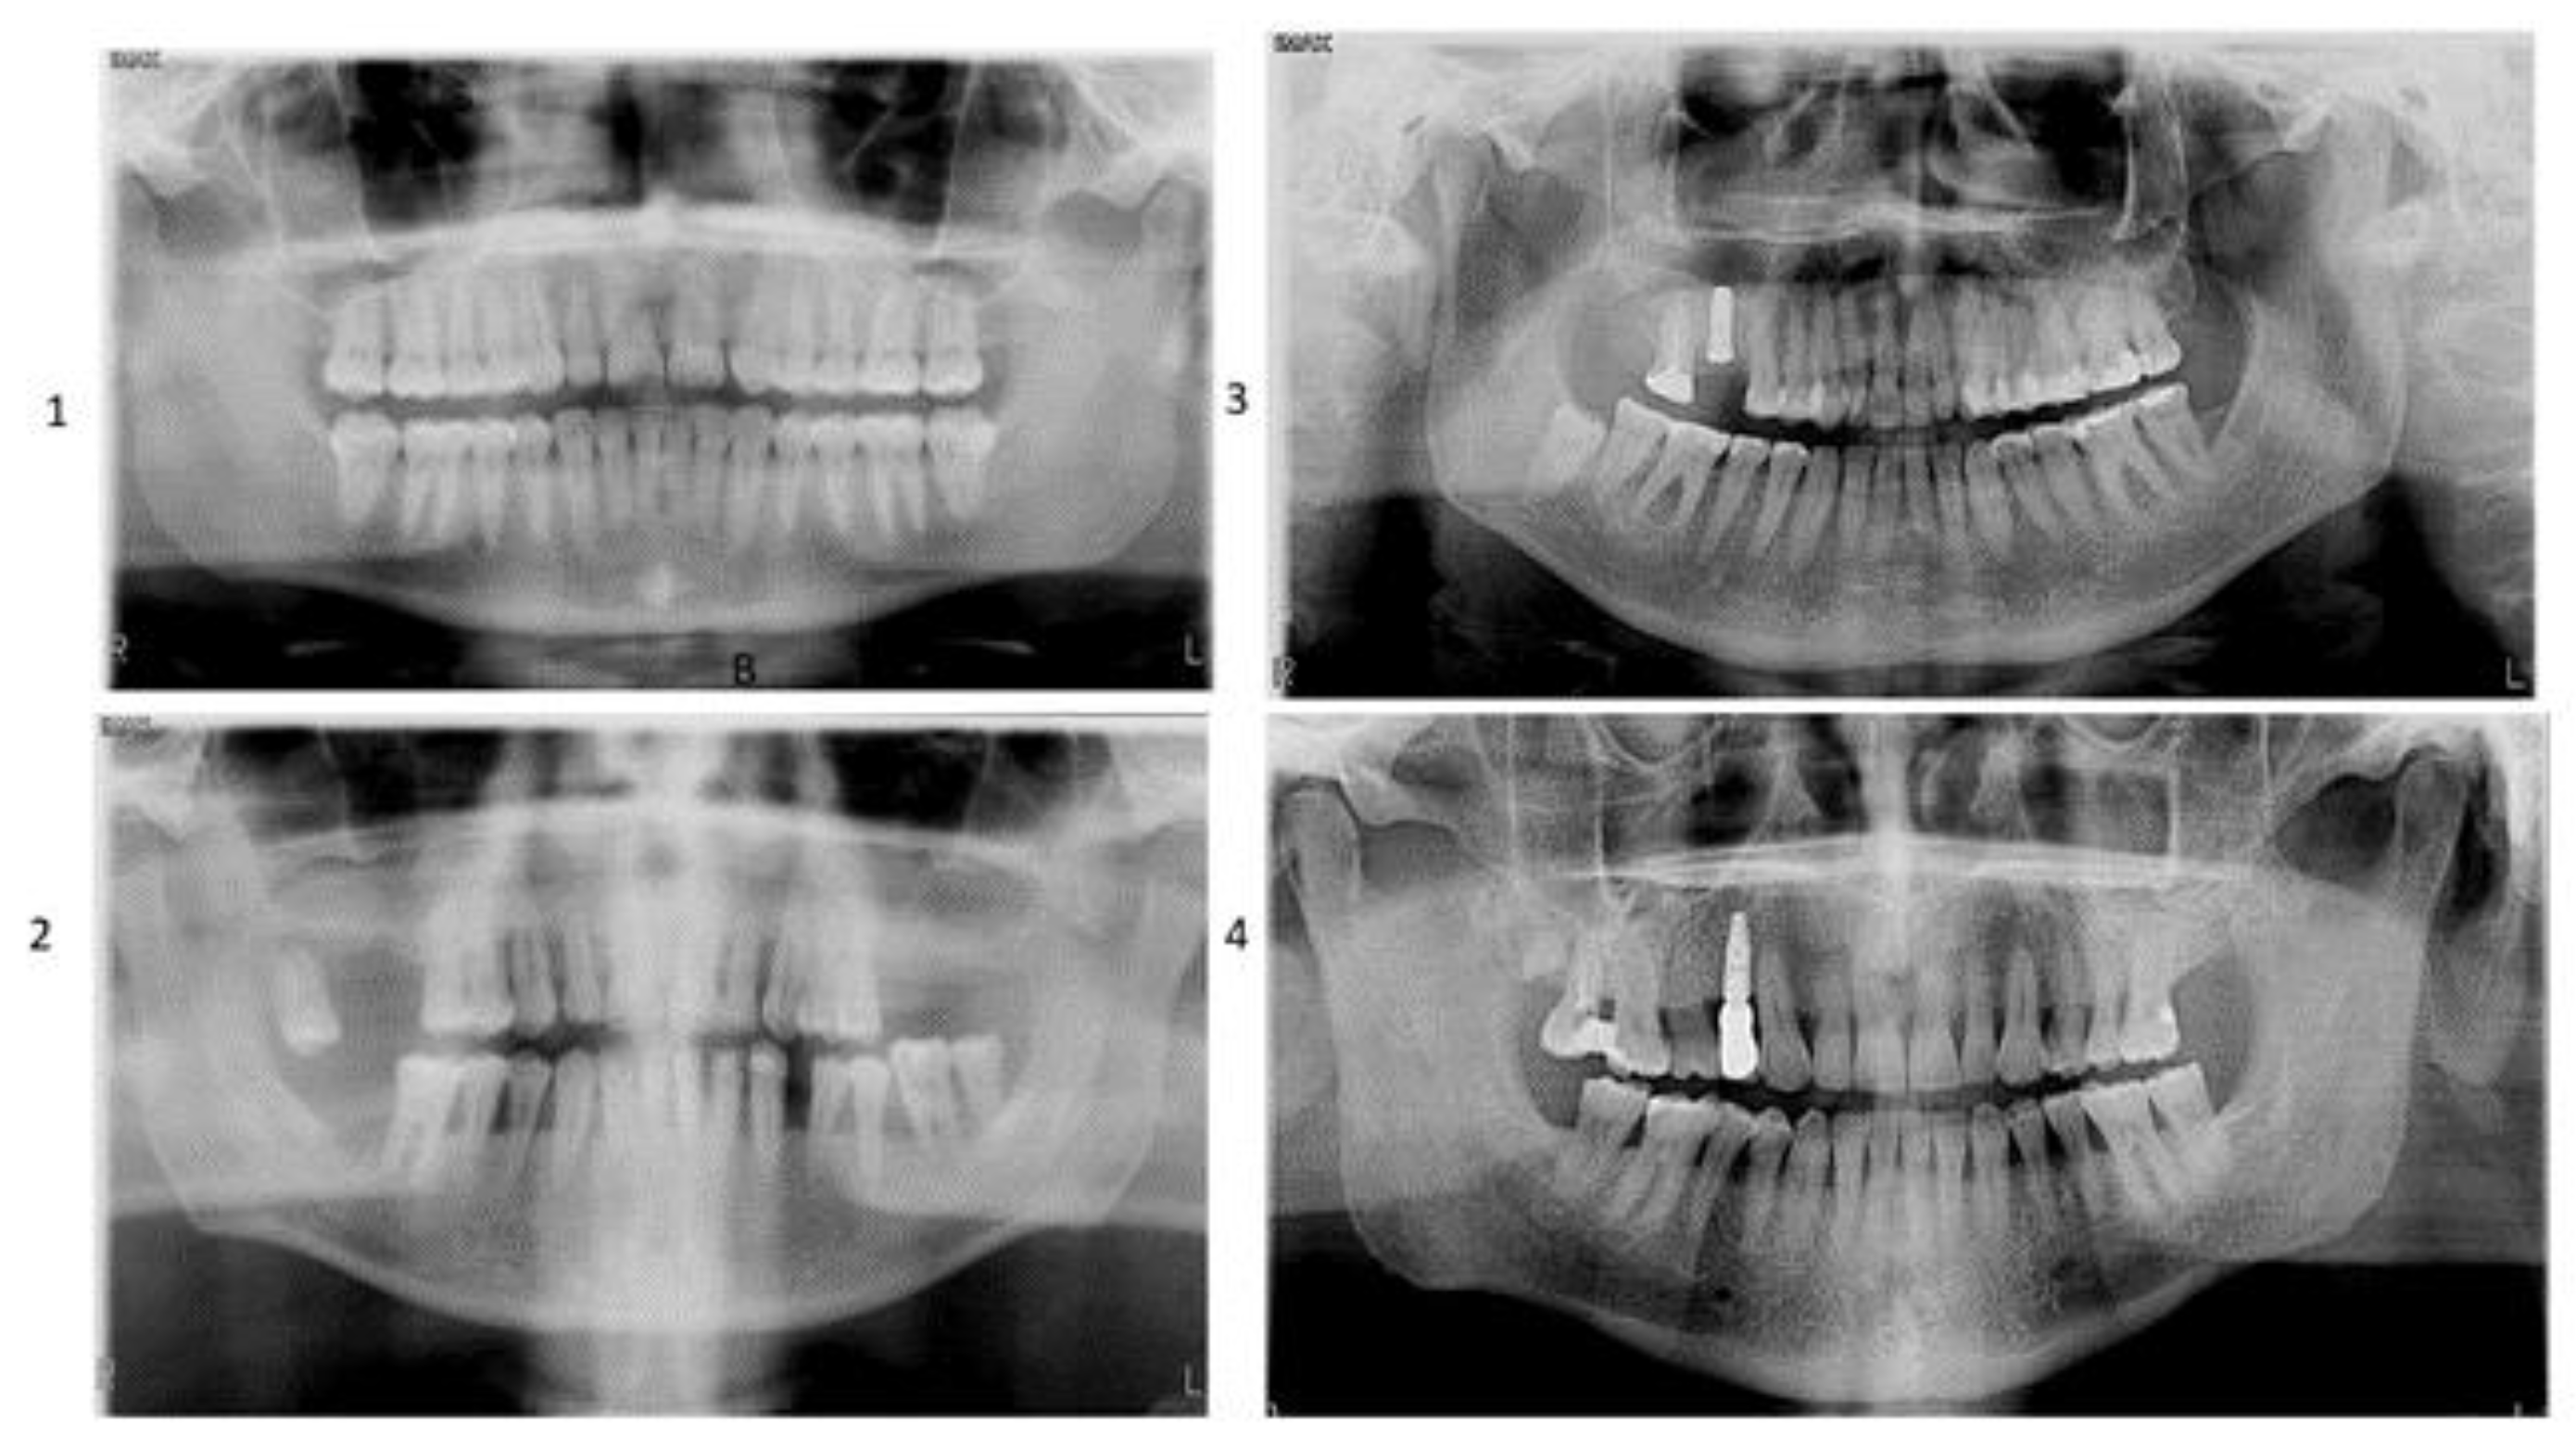

- Group 1: Healthy patients without implants (n = 40)

- Group 2: Patients undergoing periodontal maintenance without dental implants (n = 40)

- Group 3: Healthy patients with implants older than six months (n = 40)

- Group 4: Patients undergoing periodontal maintenance with implants older than six months (n = 40)